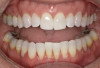

A 52-year-old female patient with history of lost retainers that she had used for a previous orthodontic treatment presented with minor orthodontic relapse during a hygiene visit. Her chief concern was that her lateral incisors were "starting to flare forward," as she had not been compliant with her retainers, and she expressed a desire for an affordable clear aligner solution. Clinically she presented with upper and lower anterior tooth crowding of less than 3 mm, specifically lower anterior teeth Nos. 23, 24, and 25, with a reverse curve of Spee of less than 2 mm on the lower anterior teeth (Figure 1 through Figure 3). The upper anterior arch presented with lateral incisor buccal rotations of less than 15 degrees on teeth Nos. 7 and 10 from an overjet view (Figure 4). The patient's oral hygiene was within normal limits, with stage one gingivitis, based on the new multidimensional staging and grading system of the American Academy of Periodontology and the European Federation of Periodontology that was adopted in 2017.12 The patient also presented with class I bite classification with gingival abfraction on both the anterior and posterior arches, with visibly missing class V restorations (Figure 5 and Figure 6).

Fig 1. Patient presented with upper and lower anterior tooth crowding

of less than 3 mm. Figure 1: Anterior view. Figure 2: Upper arch. Figure 3: Lower

arch.

Figure 1